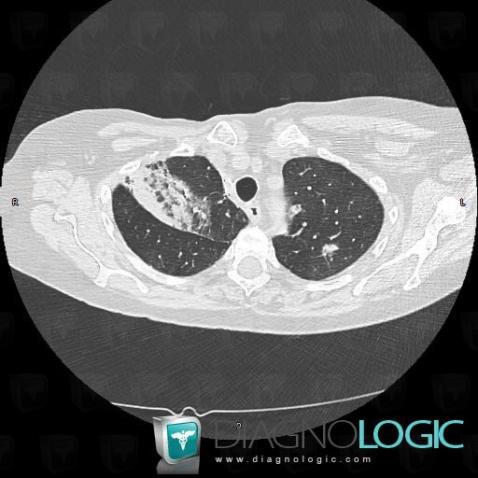

Bronchioloalveolar carcinoma, Pulmonary parenchyma, CT

Here is the specific information in the key image above:

- Diagnosis Bronchioloalveolar carcinoma, Location(s) Pulmonary parenchyma, with gamuts Solitary pulmonary mass